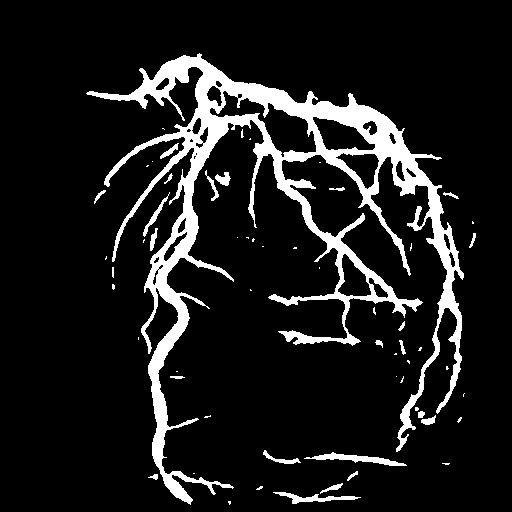

| Image | Ground truth | Video frame | Ground truth | Video frame | Ground truth |

| XCAD [33] | CADICA [19] | Our XACV dataset | |||

4.1 XACV Dataset

We collect 111 complete records of coronary artery X-ray videos, encompassing the injection, flow through the blood vessels around the heart, and dissipation of the contrast agent. Subsequently, we establish the XACV (X-ray Angiography Coronary Video) dataset. Each video consists of varying numbers of high-resolution coronary artery X-ray images. We invite experienced radiologists to annotate the vascular regions, focusing on one or two frames where the contrast agent is most prominent in each video. The XCAD dataset contains only a single image, and the CADICA video dataset does not provide corresponding ground truth. Therefore, in the following experiments, we conduct all the analyses on our collected XACV dataset and the corresponding GT for each sequence. In Figure 5, we show that compared to other publicly available datasets, XCAD [33] and CADICA [19], our dataset exhibits finer annotations in the vascular regions, providing an advantage for future related tasks. The development and use of our dataset have been approved by our institution’s IRB.